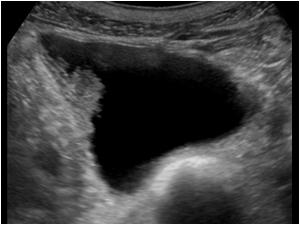

Mesanedeki Kitlenin Ultrason Görüntüsü

Mesanede kitle çoğu zaman herhangi bir belirti vermez ve genellikle başka nedenlerden dolayı yapılan ultrason gibi görüntüleme yöntemleri sırasında fark edilir. Ancak, idrarda kanama, ağrı, sık idrara çıkma gibi belirtiler görülebilir. Bu tür bir durum olduğunda ilk yapılacak iş ultrason incelemesidir.